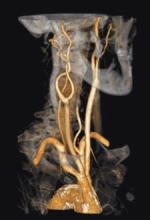

Heart disease and stroke are the first and third leading causes of death in the U.S. Atherosclerosis is the common pathological process underlying myocardial infarction, stroke and other occlusive vascular diseases. Atherosclerosis has a long latent period between early phases of the disease and the manifestation of clinical symptoms. Thus, there is an opportunity for primary prevention if patients can be identified before the first clinical event.

The good news is that hybrid imaging, one of the fastest-growing markets in medical imaging, is an effective tool for noninvasive disease detection, monitoring and therapy. The trouble is that many physicians cannot optimize the use of all the high-volume data generated because their workstations lack advanced visualization applications for rendering 3-D and 4-D images.